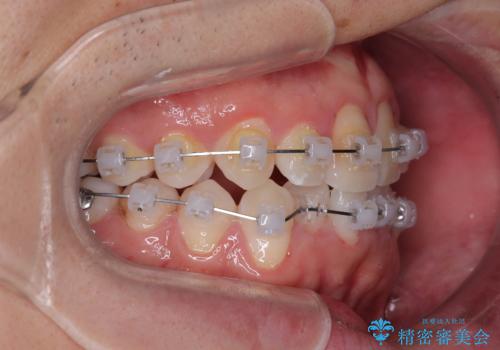

- 矯正装置

- クリアブラケット

- 「上下の前歯がガタガタしているのが気になる」とのことで来院された患者様です。

上下顎前歯部に叢生(歯の重なり・ガタつき)を認め、見た目だけでなく、歯磨きのしにくさも気にされて来院されました。

そのため今回は、プラスチックブラケット+メタルワイヤーによるクリアブラケットによる治療を選択しました。